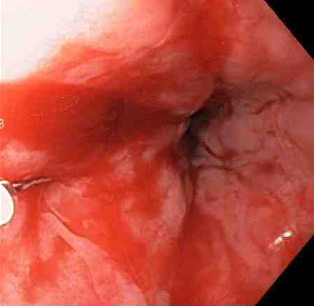

[Figure caption and citation for the preceding image starts]: Laceração de Mallory-Weiss após injeção de adrenalina (sangramento interrompido, permitindo melhor visualização da lesão)Do acervo de Juan Carlos Munoz, MD, University of Florida [Citation ends].